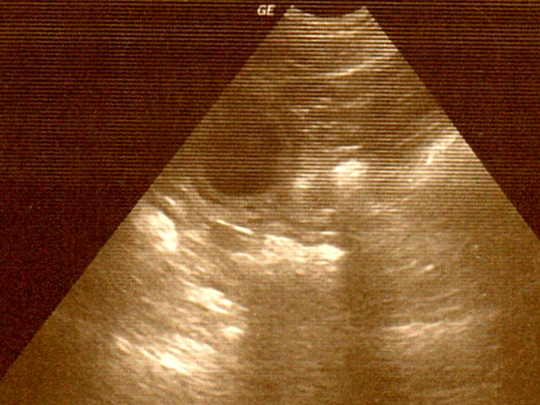

Drei Fruchtblasen waren im Ultraschall zu sehen. Es können natürlich auch mehr Welpen werden, denn meist sieht man nicht alle bei dieser Untersuchung.